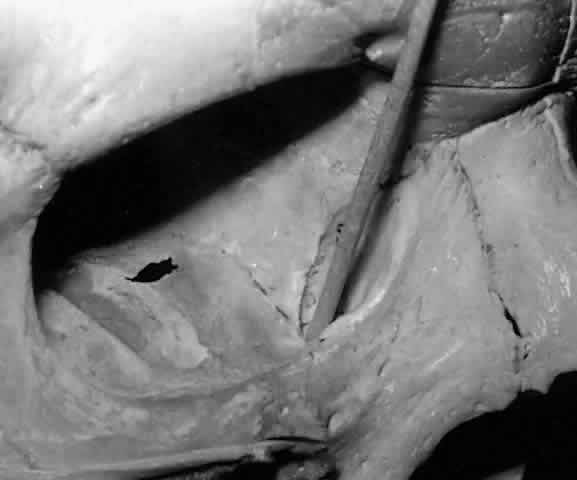

Fig. 4. The sharp anterior border of the left lacrimal gland (black arrow) rests behind the orbital septum (pointer), which in this cadaver has been reflected anteriorly.

The almond-shaped orbital lobe (see Fig. 2) represents approximately 65% to 75% of the gland and measures 20 mm long × 5 mm thick × 12 mm wide.2 Its sharp anterior border rests behind the superior orbital rim and is covered by the orbital septum (Fig. 4) and a portion of the temporal aspect of the central preaponeurotic fat pad (Fig. 5). Posteriorly, its rounded border is supported by a large superotemporal fat pad at the plane of the posterior pole of the globe.3 The convex superior surface is suspended from the periorbita of the lacrimal gland fossa of the frontal bone. The inferior border is convex and attached to the sheath of the levator aponeurosis. Its lateral border is smooth and convex in contour with the bony fossa.